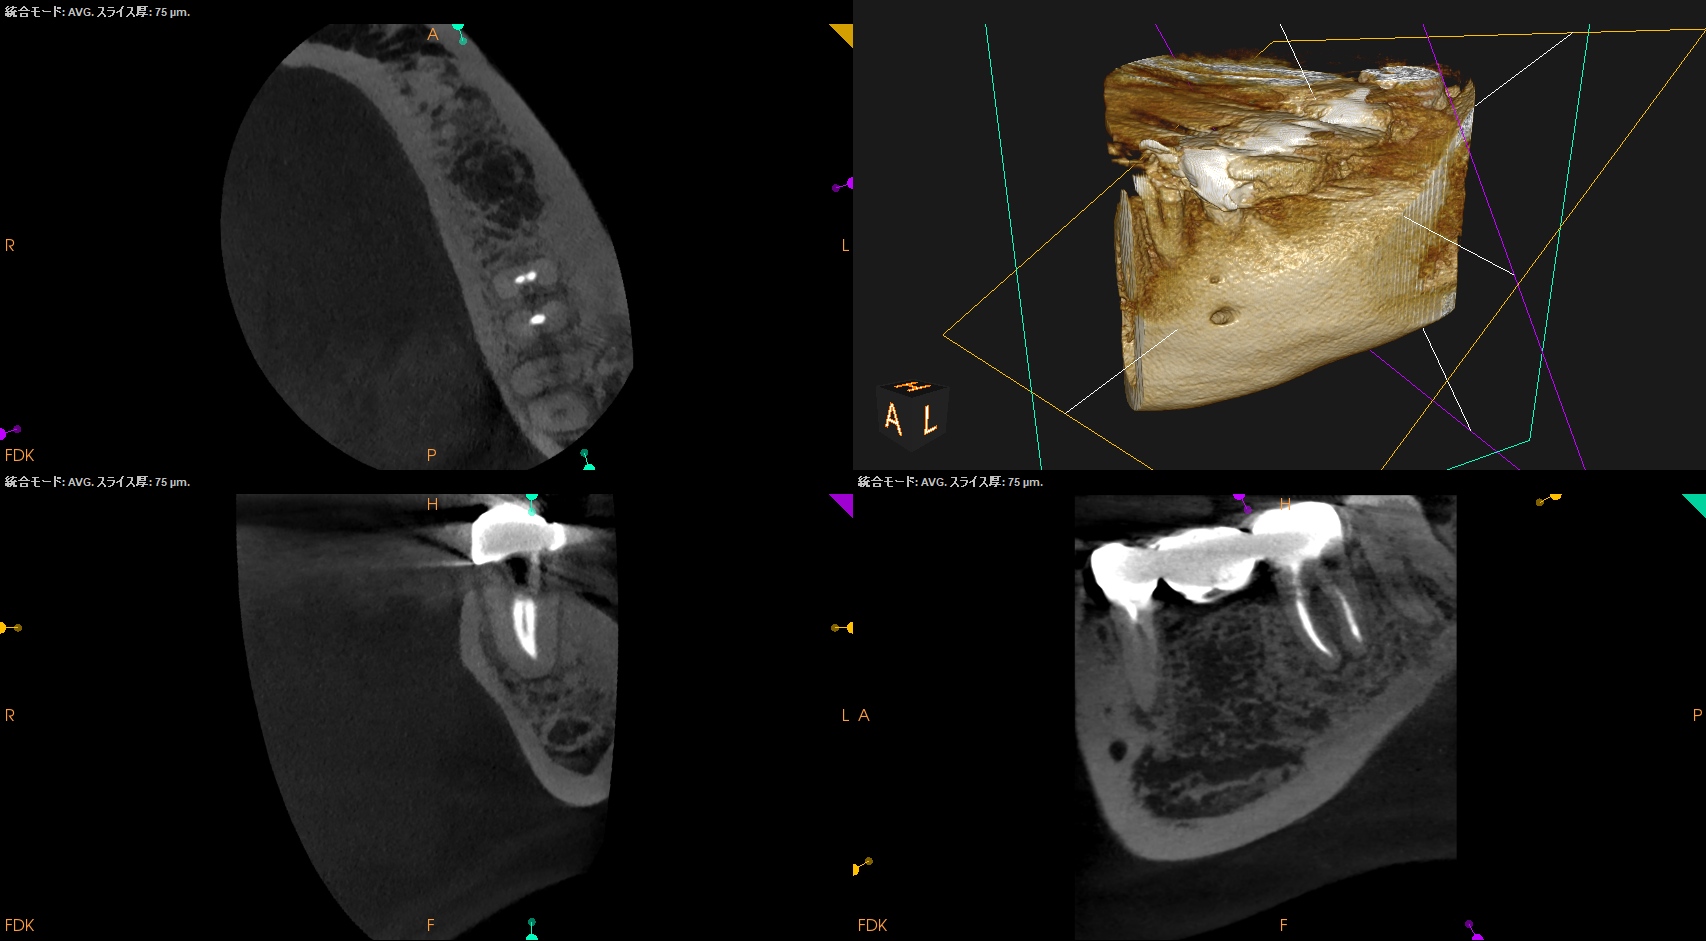

Post-op 1yr recall(2025.1.29)

MB

ML

D

初診時と比較した。

大きく状況は改善された。